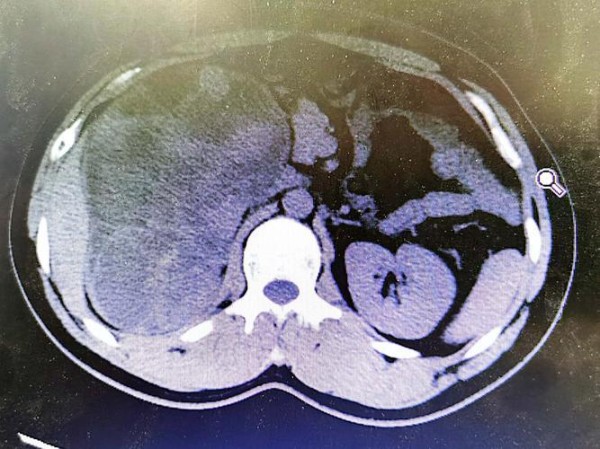

在3月16日傍晚,法国一家医院里,年仅43岁的比利时女演员艾米莉·德奎恩因病离世,死因是罕见的且恶性程度极高的肾上腺皮质癌。她的家人和经纪人在社交媒体上公布了这一消息。从2023年8月被确诊到最终离世,她与病魔抗争了短短一年多的时间。

艾米莉·德奎恩的病例中,所患的肾上腺皮质癌虽然属于罕见情况,但这也提醒我们,身体内部可能长期存在的隐患往往因忽视而未能及时发现。同时,现代人普遍面临的工作压力也是一个不容忽视的健康隐患。无论是明星还是普通人,都深受其影响。